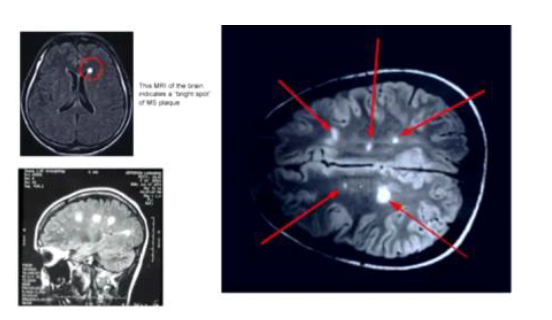

What does MS look like on MRI?